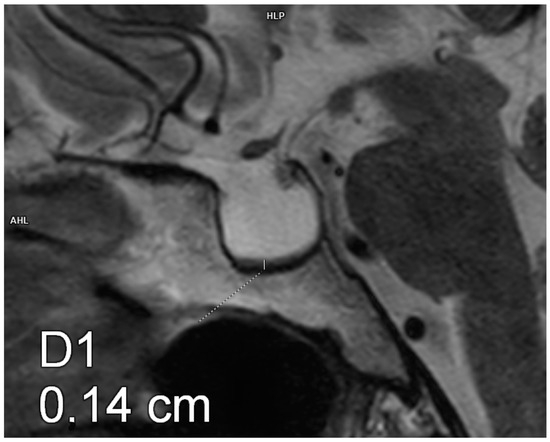

Figure 2.

Partial empty sella. Magnetic resonance imaging, T2-weighted image, sagittal plane. The craniocaudal diameter of the pituitary gland is 3.5 mm.